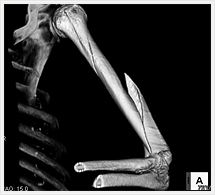

画像紹介

CTでは輪切り像の他にも立体的な画像(3D画像)を作成することもできます。そのためにはより細かくキレイな画像を撮影しなければなりません。当院では64列CTを導入しており、キレイな画像をより細かく撮影することができます。その画像を元に3D画像を作成することによって、より正確な手術のシミュレーションが可能になります。実際に手術をしたときの様子が、手術をする前に画像として見らます。外科系の手術には欠かせない技術となっておりますが、内科系でも血管内手術にも多く利用されております。

当診療放射線技術科では毎日各診療科に対して、その手術に最適な3D画像を提供しております。

以下にその3D画像を一部分紹介します。

四肢